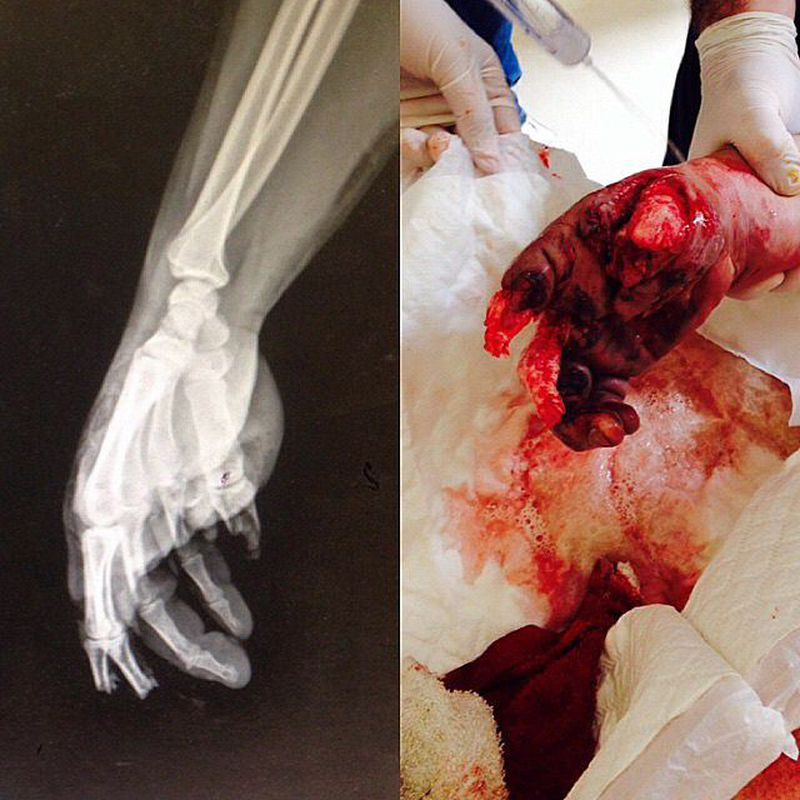

Explosive blast causes a pattern of injury including primary blast lung, secondary fragment injury and traumatic amputation of limbs. Major traumatic amputation is rare in survivors of bomb blast but common in those who die. The mechanism of such injury has not been previously determined.Patients who survived to reach medical care after blast injury was investigated to determine the anatomical level of amputation and the pattern of soft tissue damage. Joints were an infrequent site of amputation and the tibial tuberosity was a particularly frequent site of lower-limb severance. The accepted mechanism of traumatic amputation, avulsion by the dynamic overpressure, is challenged. Photo Credit - @ksven_official